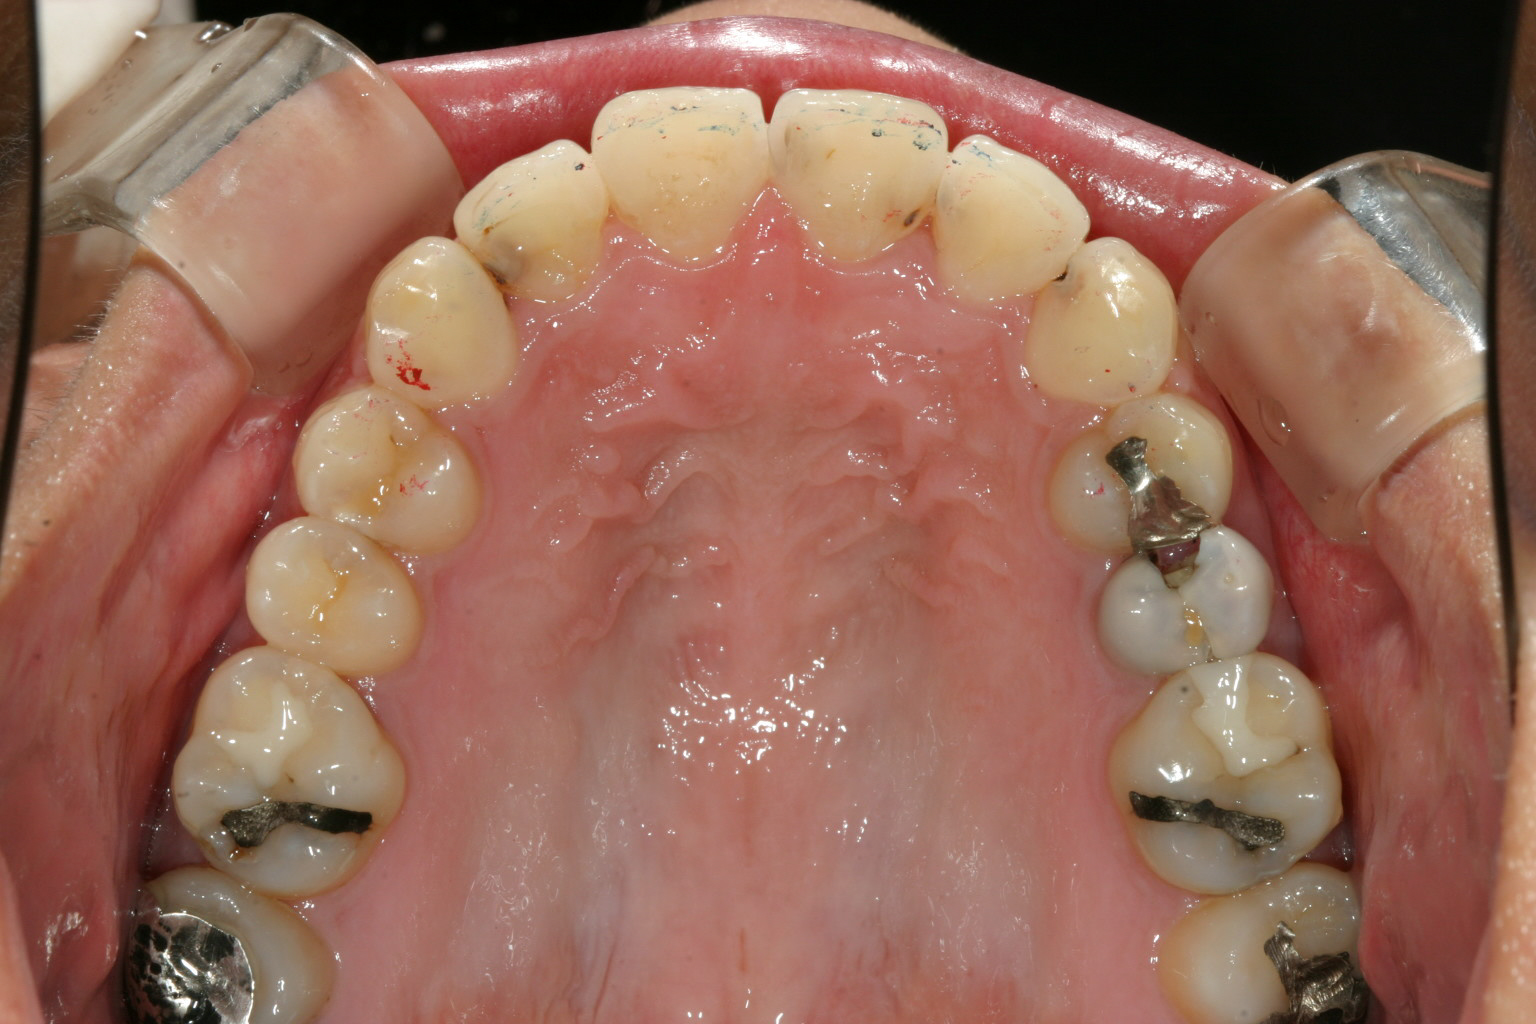

アーチを広げる事により綺麗に改善です。

こういうケースはさほど難しく無くアーチを拡大するのと全体的な前突を改善する為にIPR(歯と歯の隙間を削る)をする事により

抜歯する事無く出っ歯感を改善します。